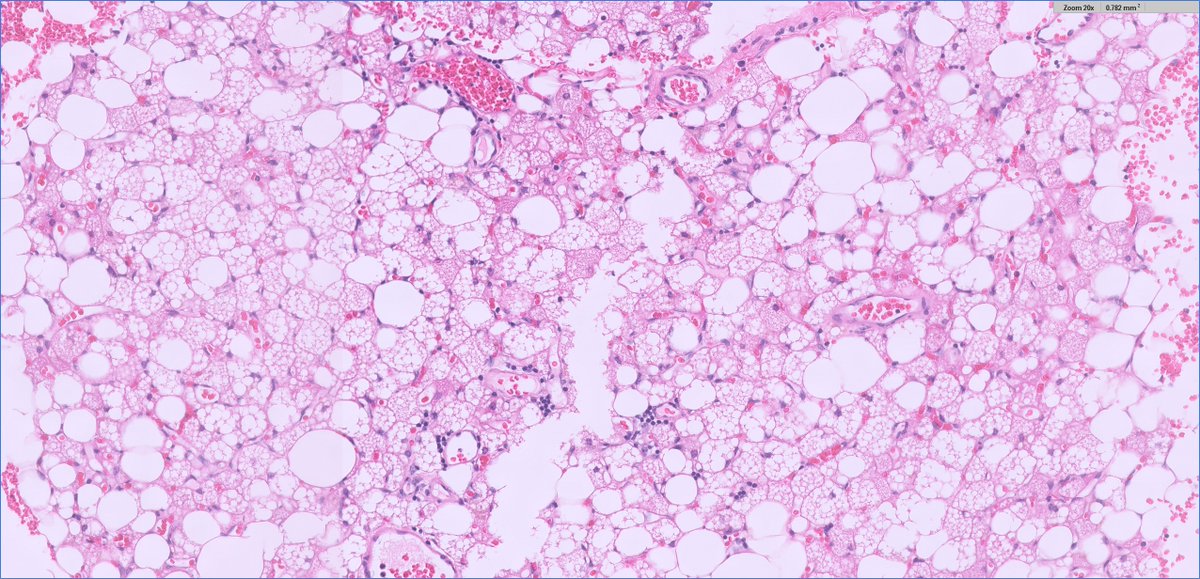

#endopath: adrenal myelolipoma

adrenal myelolipoma